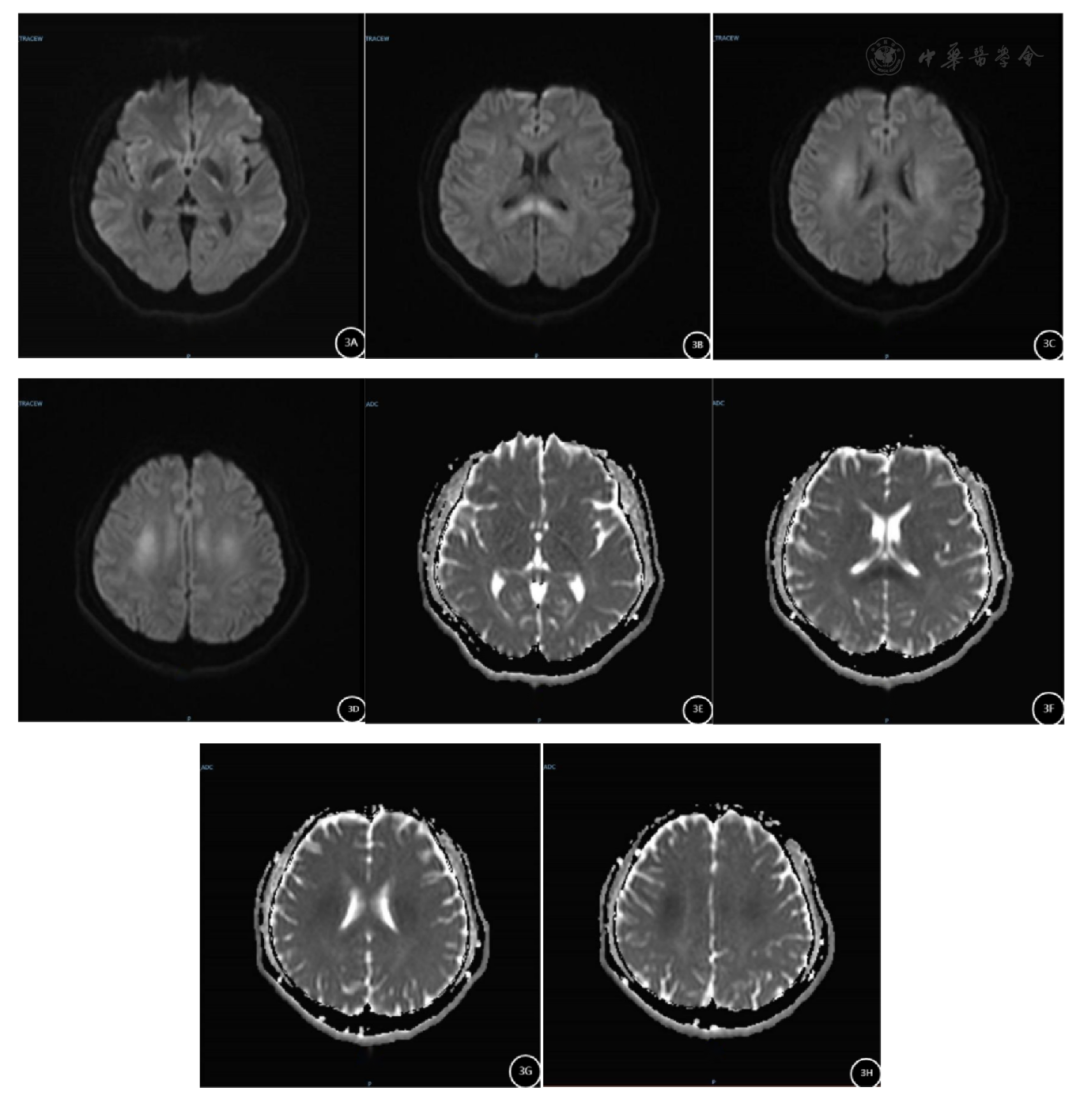

发病第6天,头部MRI平扫提示相应病变区域范围减少,信号较前减弱,强度降低(图3)。化验:激酶、肝功、肾功能指标较前明显改善:ALT 104U/L,AST 129U/L,CK 5969U/L,CK-MB 72U/L,CR 87.7μmol/L,BUN 9.9mmol/L,UA 579μmol/L,同日,毒物分析提示血液和尿液标本可见微量氟乙酰胺成分,未检出溴鼠灵、溴敌隆和敌鼠钠成分;脑电图未见明显痫样波,诱发电位可见部分交感和副交感功能障碍。

图3 患者发病第6天头部MRI平扫情况

提示双侧桥臂、双侧大脑脚、双侧内囊后肢、双侧脑室周围白质、双侧半卵圆中心和胼胝体,相应病变区域范围减少,信号较前减弱,强度降低

A~D:显示核磁DWI信号;

E~H:显示核磁ADC信号